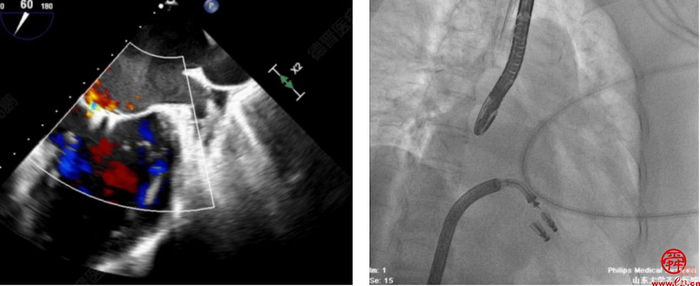

术中全麻成功后,穿刺右股静脉,在超声和射线辅助下成功穿刺房间隔。使用血管鞘相继扩张股静脉后,经超硬导丝导入24F导引鞘并且成功进入左房。在经食道超声辅助下,在2区成功夹闭二尖瓣返流区域,释放2枚二尖瓣瓣膜夹。

术后,患者反流程度从4+转至1+,即刻超声提示二尖瓣返流量下降到轻度,跨二尖瓣平均压差4mmHg。手术操作时间110分钟,透视时间总计为9分钟,手术取得成功。